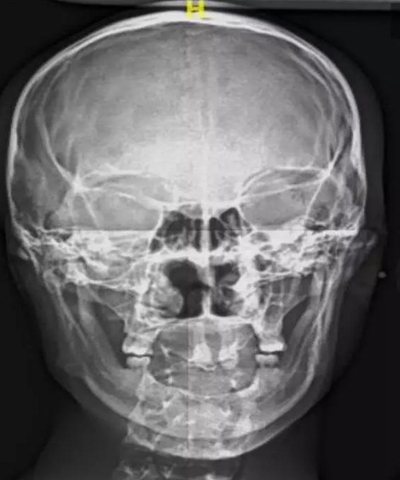

病例概要:患者,男,23歲,先天性多數(shù)恒牙缺失,外胚層發(fā)育不全,上下頜牙槽骨寬度及高度發(fā)育嚴(yán)重不足,佩戴傳統(tǒng)活動義齒固位穩(wěn)定效果差,幾乎沒有咀嚼功能,需通過種植修復(fù)來改善上述情況?;颊呒揖池毢?,所涉及的種植手術(shù)相關(guān)材料費(fèi)

用高,需要得到社會慈善機(jī)構(gòu)的幫助,才能獲得種植治療的可能。

病例資料:患者,男,23歲,先天性多數(shù)恒牙缺失,影響咀嚼和美觀功能。無恒牙拔牙史,無系統(tǒng)性疾病史,身體健康,無藥物過敏史。

??茩z查:口內(nèi)僅剩16,11,21,26,雙側(cè)上下頜乳牙E滯留,其余恒牙缺失,上下頜骨發(fā)育不足,缺牙區(qū)牙槽嵴呈刃狀,上下頜弓比例協(xié)調(diào)。CBCT顯示:上頜前牙區(qū)牙槽嵴寬度約2-3mm,骨高度約10mm;上頜后牙區(qū)可用牙槽骨高度僅1-2mm,左右側(cè)上頜

竇內(nèi)粘膜有明顯增厚。下頜牙槽骨寬度及高度嚴(yán)重不足,僅存有基骨。

病例難點(diǎn):

該病例為外胚層發(fā)育不全患者,先天性全口多數(shù)牙缺失,患者口內(nèi)僅剩4個恒牙,4個乳牙,勉強(qiáng)維持咬合功能。牙槽骨發(fā)育嚴(yán)重不足,垂直向和水平向骨缺損顯著。如果應(yīng)用常規(guī)的種植方法需要在前牙區(qū)和后牙區(qū)進(jìn)行大范圍的植骨手術(shù),整個治療周

期將長達(dá)一年或以上,費(fèi)用高。這類患者口內(nèi)來源的骨量非常有限,如果進(jìn)行自體骨移植,則需要另外增加一個口外供骨區(qū),增加了患者的痛苦,治療效果也難以保證。此外,經(jīng)驗(yàn)表明,外胚層發(fā)育不全的患者行骨增量往往成骨效果差,療效甚微。

由于牙槽骨寬度嚴(yán)重不足,短種植體不適用于此類患者。因此,上述病例屬于難度極高的種植對象,讓很多種植醫(yī)生一籌莫展。